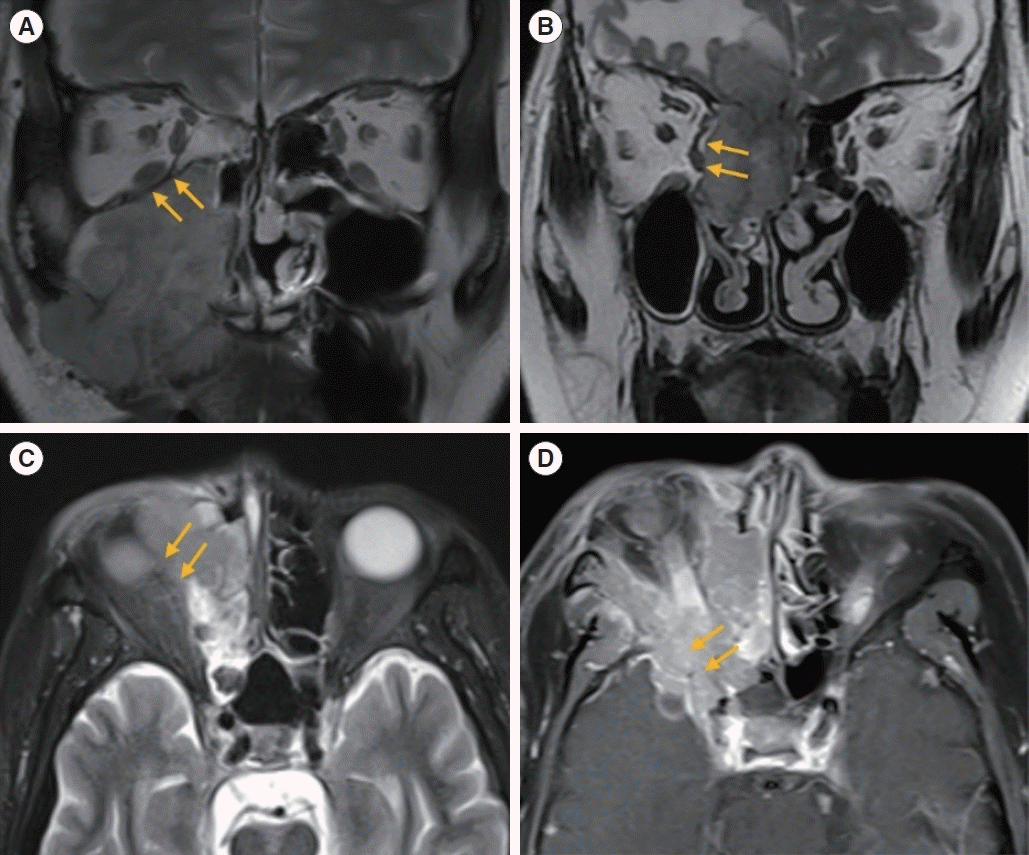

Fig. 1.

Fig. 2.

Fig. 3.

Fig. 4.

Fig. 5.